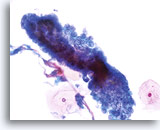

Adenocarcinoma in situ

Endocervical cells presenting in a strip with pronounced nuclear crowding. Biopsy – AIS – 60x